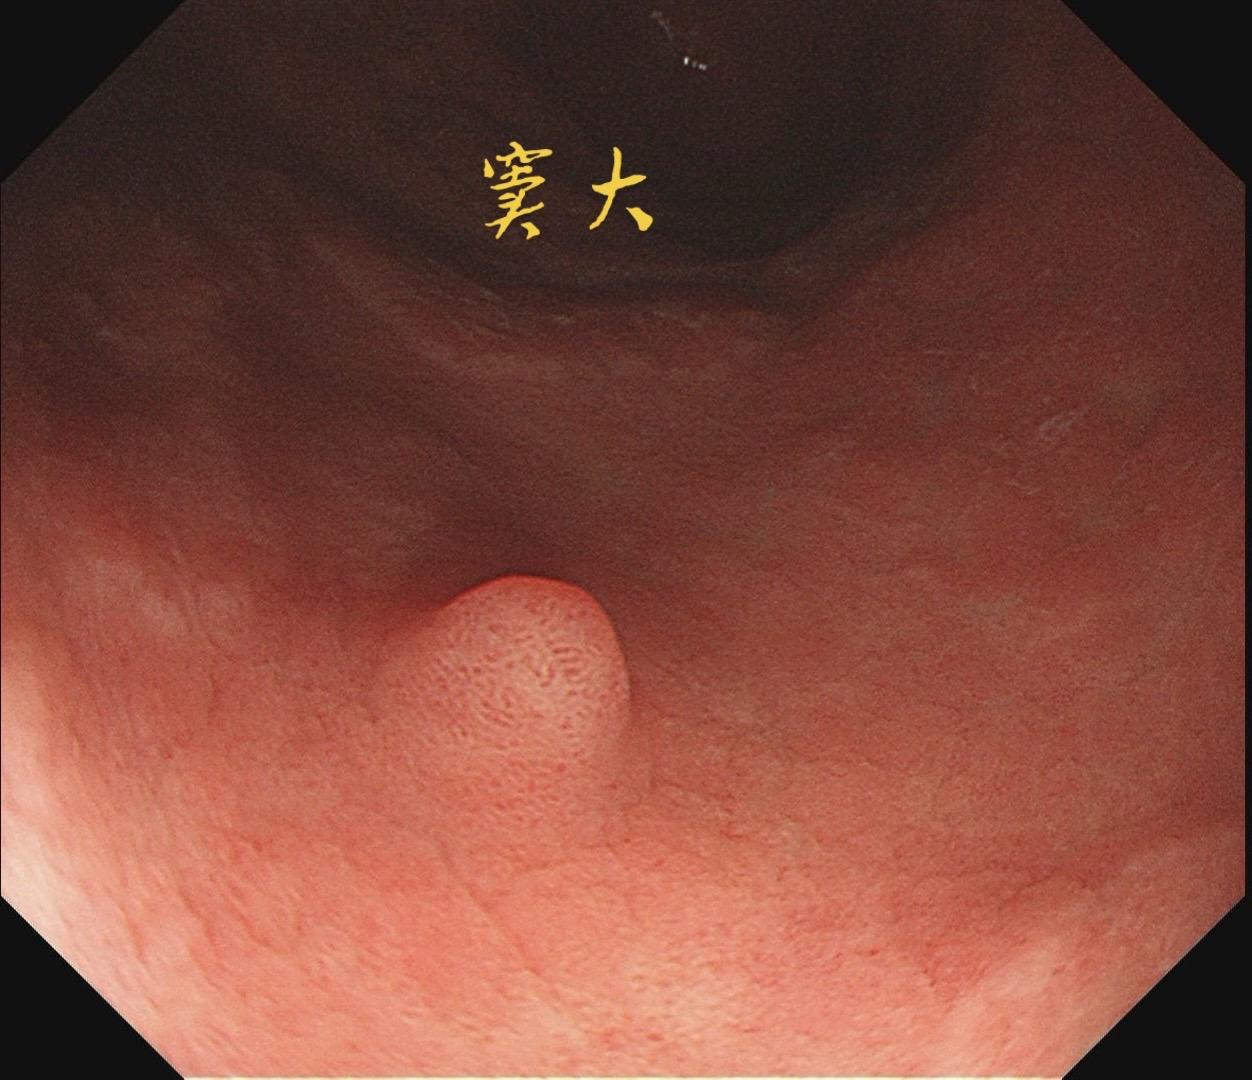

男,61岁,胃巨大褪色调病变。答案在最后一张图片,你猜对了吗? 患者因上腹部饱胀行胃镜检查,Hp阴性背景,胃窦至贲门下见一巨大褪色调病变,边界清晰,病变相对表浅,未见明显溃疡及隆起,胃壁较柔软,充气顺应性佳,予多点活检确诊,拟外科手术行全胃切除。做这么多年胃镜,还是第一次遇到这样的……